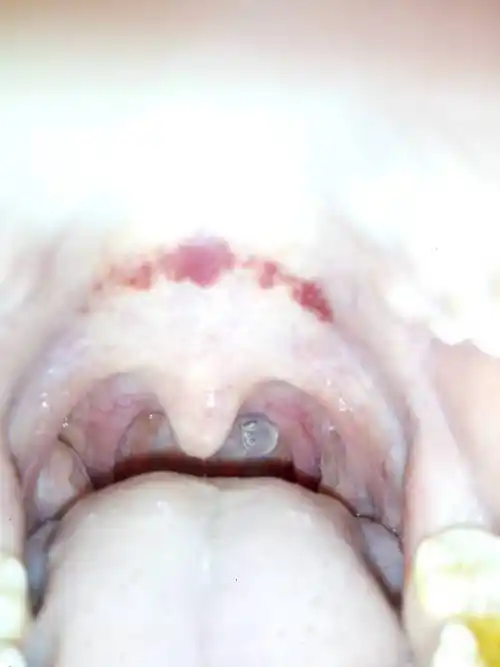

喉咙上面痛,红了,昨晚打了很多哈欠,还流鼻涕,现在